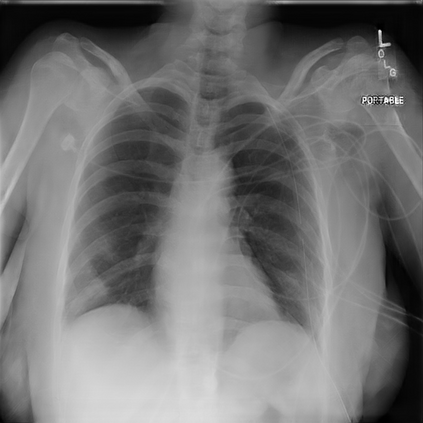

With the ongoing rise of machine learning, the need for methods for explaining decisions made by artificial intelligence systems is becoming a more and more important topic. Especially for image classification tasks, many state-of-the-art tools to explain such classifiers rely on visual highlighting of important areas of the input data. Contrary, counterfactual explanation systems try to enable a counterfactual reasoning by modifying the input image in a way such that the classifier would have made a different prediction. By doing so, the users of counterfactual explanation systems are equipped with a completely different kind of explanatory information. However, methods for generating realistic counterfactual explanations for image classifiers are still rare. Especially in medical contexts, where relevant information often consists of textural and structural information, high-quality counterfactual images have the potential to give meaningful insights into decision processes. In this work, we present GANterfactual, an approach to generate such counterfactual image explanations based on adversarial image-to-image translation techniques. Additionally, we conduct a user study to evaluate our approach in an exemplary medical use case. Our results show that, in the chosen medical use-case, counterfactual explanations lead to significantly better results regarding mental models, explanation satisfaction, trust, emotions, and self-efficacy than two state-of-the-art systems that work with saliency maps, namely LIME and LRP.